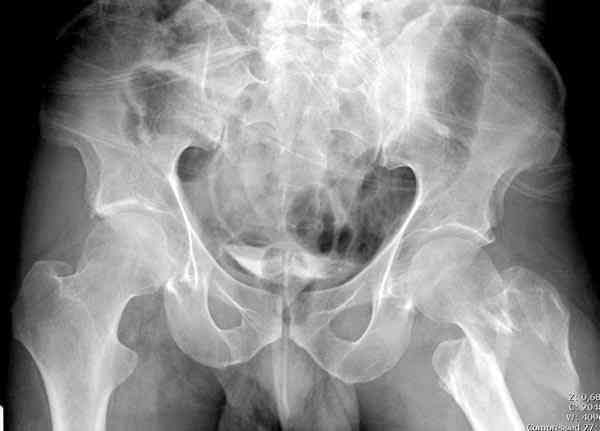

Re: [1/3] Перелом проксимального бедра

Репозиция закрытая или минимально инвазивная насколько это возможно, с джойстиками поллерами и т.п. Остеосинтез PFN, PFNa, TFN, AFN, LFN,TGN... Полную нагрузку осрочить минимум на 2-3 месяца, далее смотреть по клинике и рентгенограммам...

При открытой репозиции вероятность анатомичной репозиции не велика, а вероятность получить аваскуляную кость - очень даже.

Молиборскийй В. 30 Апрель 2006, 06:09

Gamma стержень даже короткий а нагрузку через полтора месяца постепенно

Перелом A3(AO classification of the femur proximal segment) нестабильный поэтому даже при очень хорошем остеосинтэзе нельзя давать нагрузку миним полтора месяца